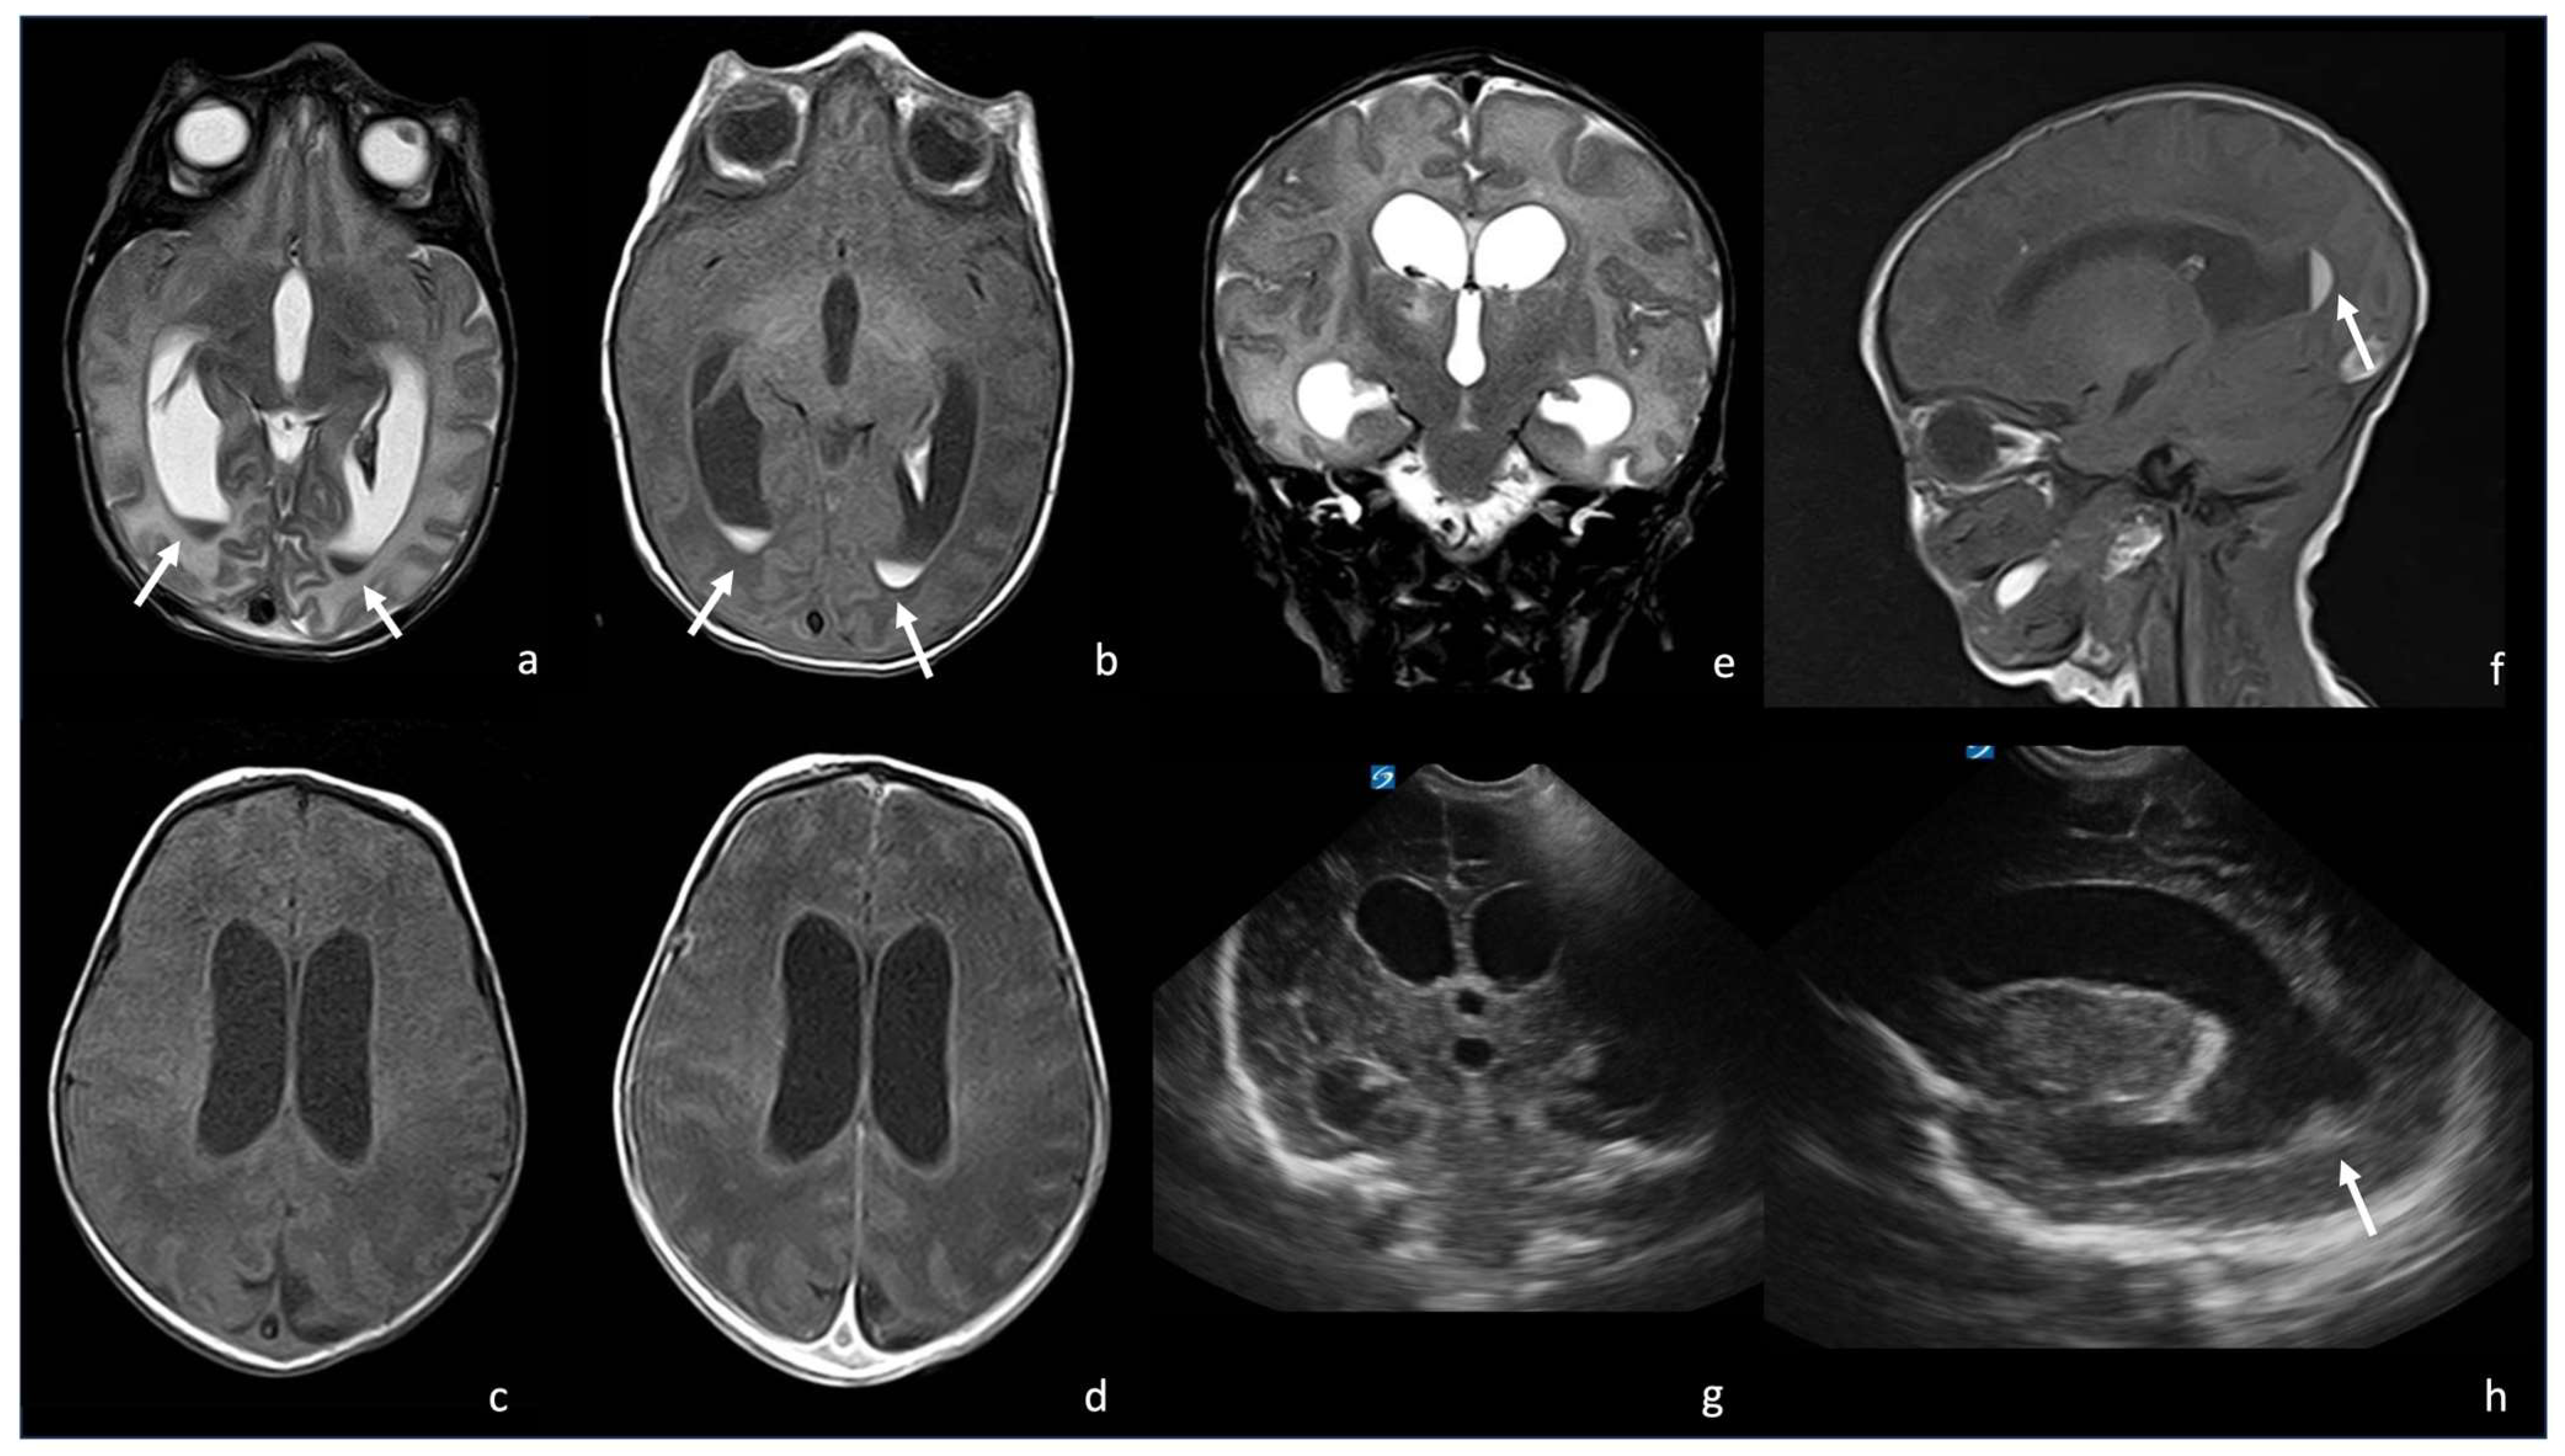

5.1. Choroid Plexitis and Ventriculitis

5.2. Meninges Involvement

5.3. Ventriculomegaly and Hydrocephalus

5.4. Effusions and Empyema